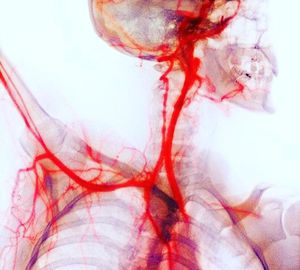

The bones (purple) are also seen on the X-ray, aiding identification of the arteries. The head (upper right) has been turned to one side to expose the right-hand side of the neck and its carotid arteries (internal and external). These arteries bring oxygenated blood to the head. The right arm (centre left) has been raised to show how the subclavian artery passes under the collar bone (clavicle) and into the arm. The arteries carry oxygenated blood from the heart (not seen). The arteries have been highlighted arteriographically by injecting them with a radio-opaque dye, creating a medium to absorb the X-rays. 📷•Medicogram• #letslearn #angiogram #xray #arteriogram #surgery #trending #now #medicine #medicogram